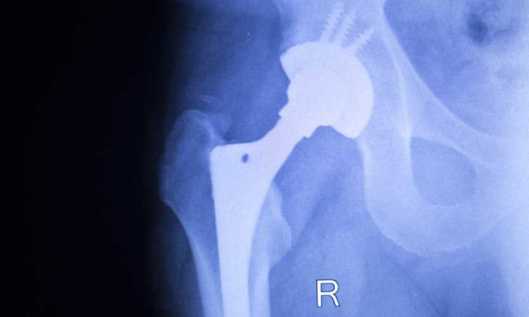

London-based Smith & Nephew Inc. develops and manufactures joint replacement systems including the Birmingham Hip Resurfacing System, which is a metal-on-metal hip replacement system that requires premarket approval from the Food & Drug Administration before it can be made commercially available, according to Monday’s ruling by the 11th U.S. Circuit Court of appeals in Atlanta in Joseph Mink v. Smith & Nephew Inc.

As time passed, Mr. Mink experienced blood toxicity from the chromium and cobalt leaching from the system, eye problems and an enlarged lymph node near the site of his hip replacement. He had to have the system removed in November 2014.